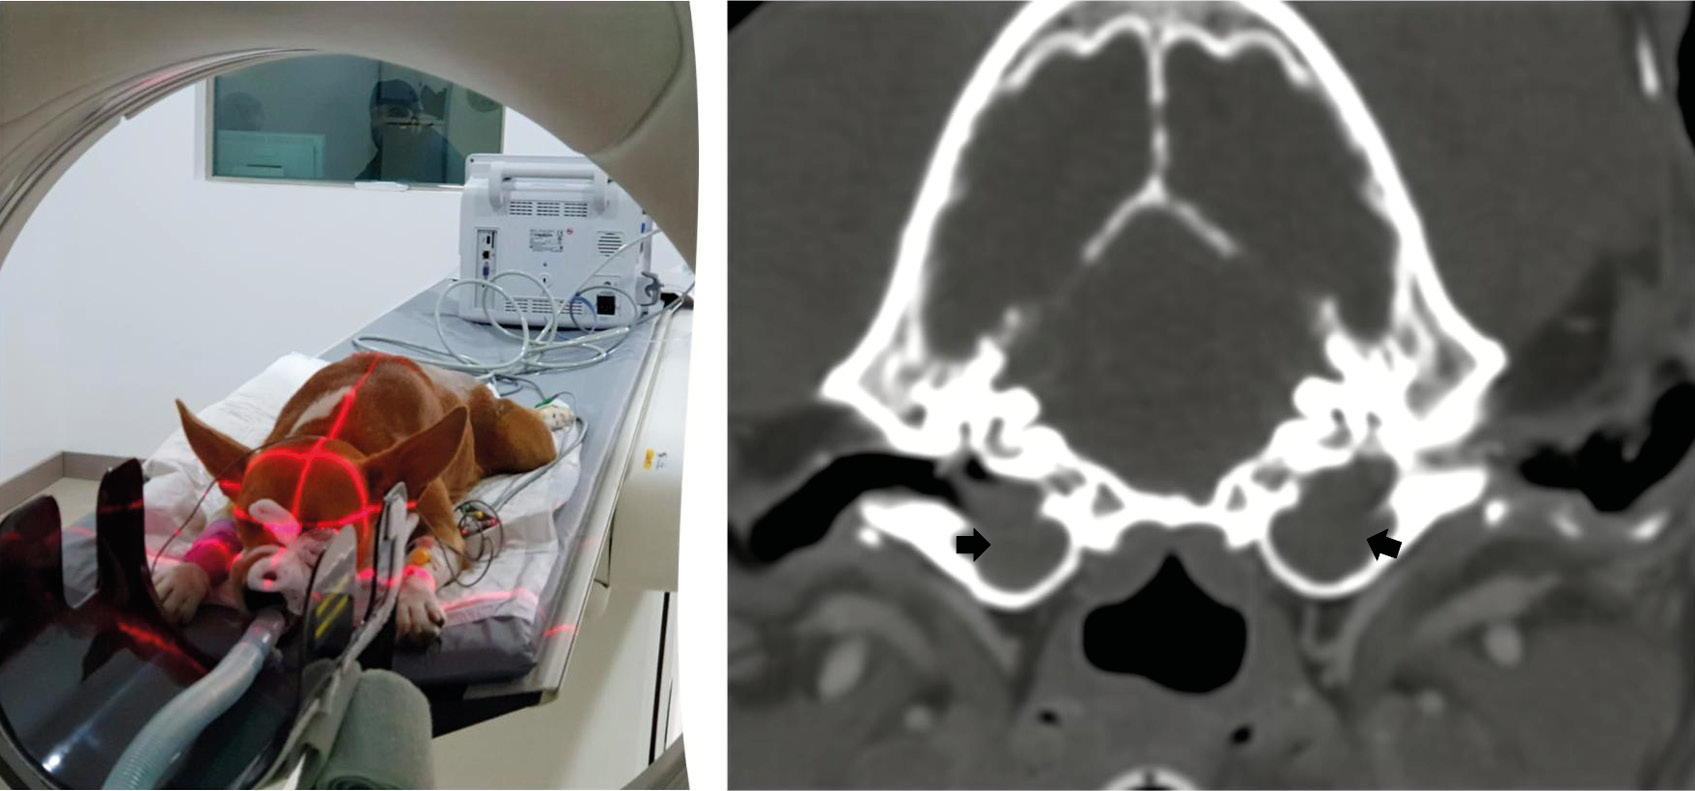

La tomografía computarizada (TC) se considera la técnica de referencia para el estudio de las estructuras del oído medio. Permite valorar la integridad y el grosor del tímpano, la presencia de contenido líquido en oído medio, masas y alteraciones en la estructura ósea de la bulla y huesos adyacentes mediante la visualización de las estructuras anatómicas en sección transversal, evitando la superposición de estructuras característica de las radiografías.

El estudio de bullas timpánicas utiliza imágenes transversales contiguas de 1 a 3 mm, desde el área rostral a la bulla hasta el hueso temporal petroso. Se recomienda usar el campo de visión más pequeño posible y una técnica de alta densidad de mAs. El contraste yodado no suele administrarse, salvo sospecha de neoplasia u otitis interna. Las imágenes deben revisarse tanto en ventana ósea como de tejido blando.

En una posición adecuada en pacientes sin patología auricular ambas bullas se observan simétricas, permitiendo pequeñas variaciones anatómicas. El gas generalmente opaca la luz de la bulla timpánica y del conducto auditivo externo. La bulla timpánica presenta una pared delgada y delimitada. El conducto auditivo externo mantiene un grosor uniforme, sin evidencia de estrechamiento ni obstrucción luminal.

Los hallazgos tomográficos característicos de la otitis media comprenden el engrosamiento y la irregularidad de la pared de la bulla timpánica, la lisis ósea, presencia de material de densidad de tejido blando compatible con líquido o contenido tisular en su interior, así como signos asociados de otitis externa (imagen 8).